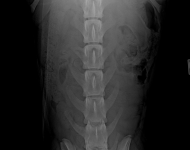

MVDr. Meloun: Lumbosakrální přechodový obratel